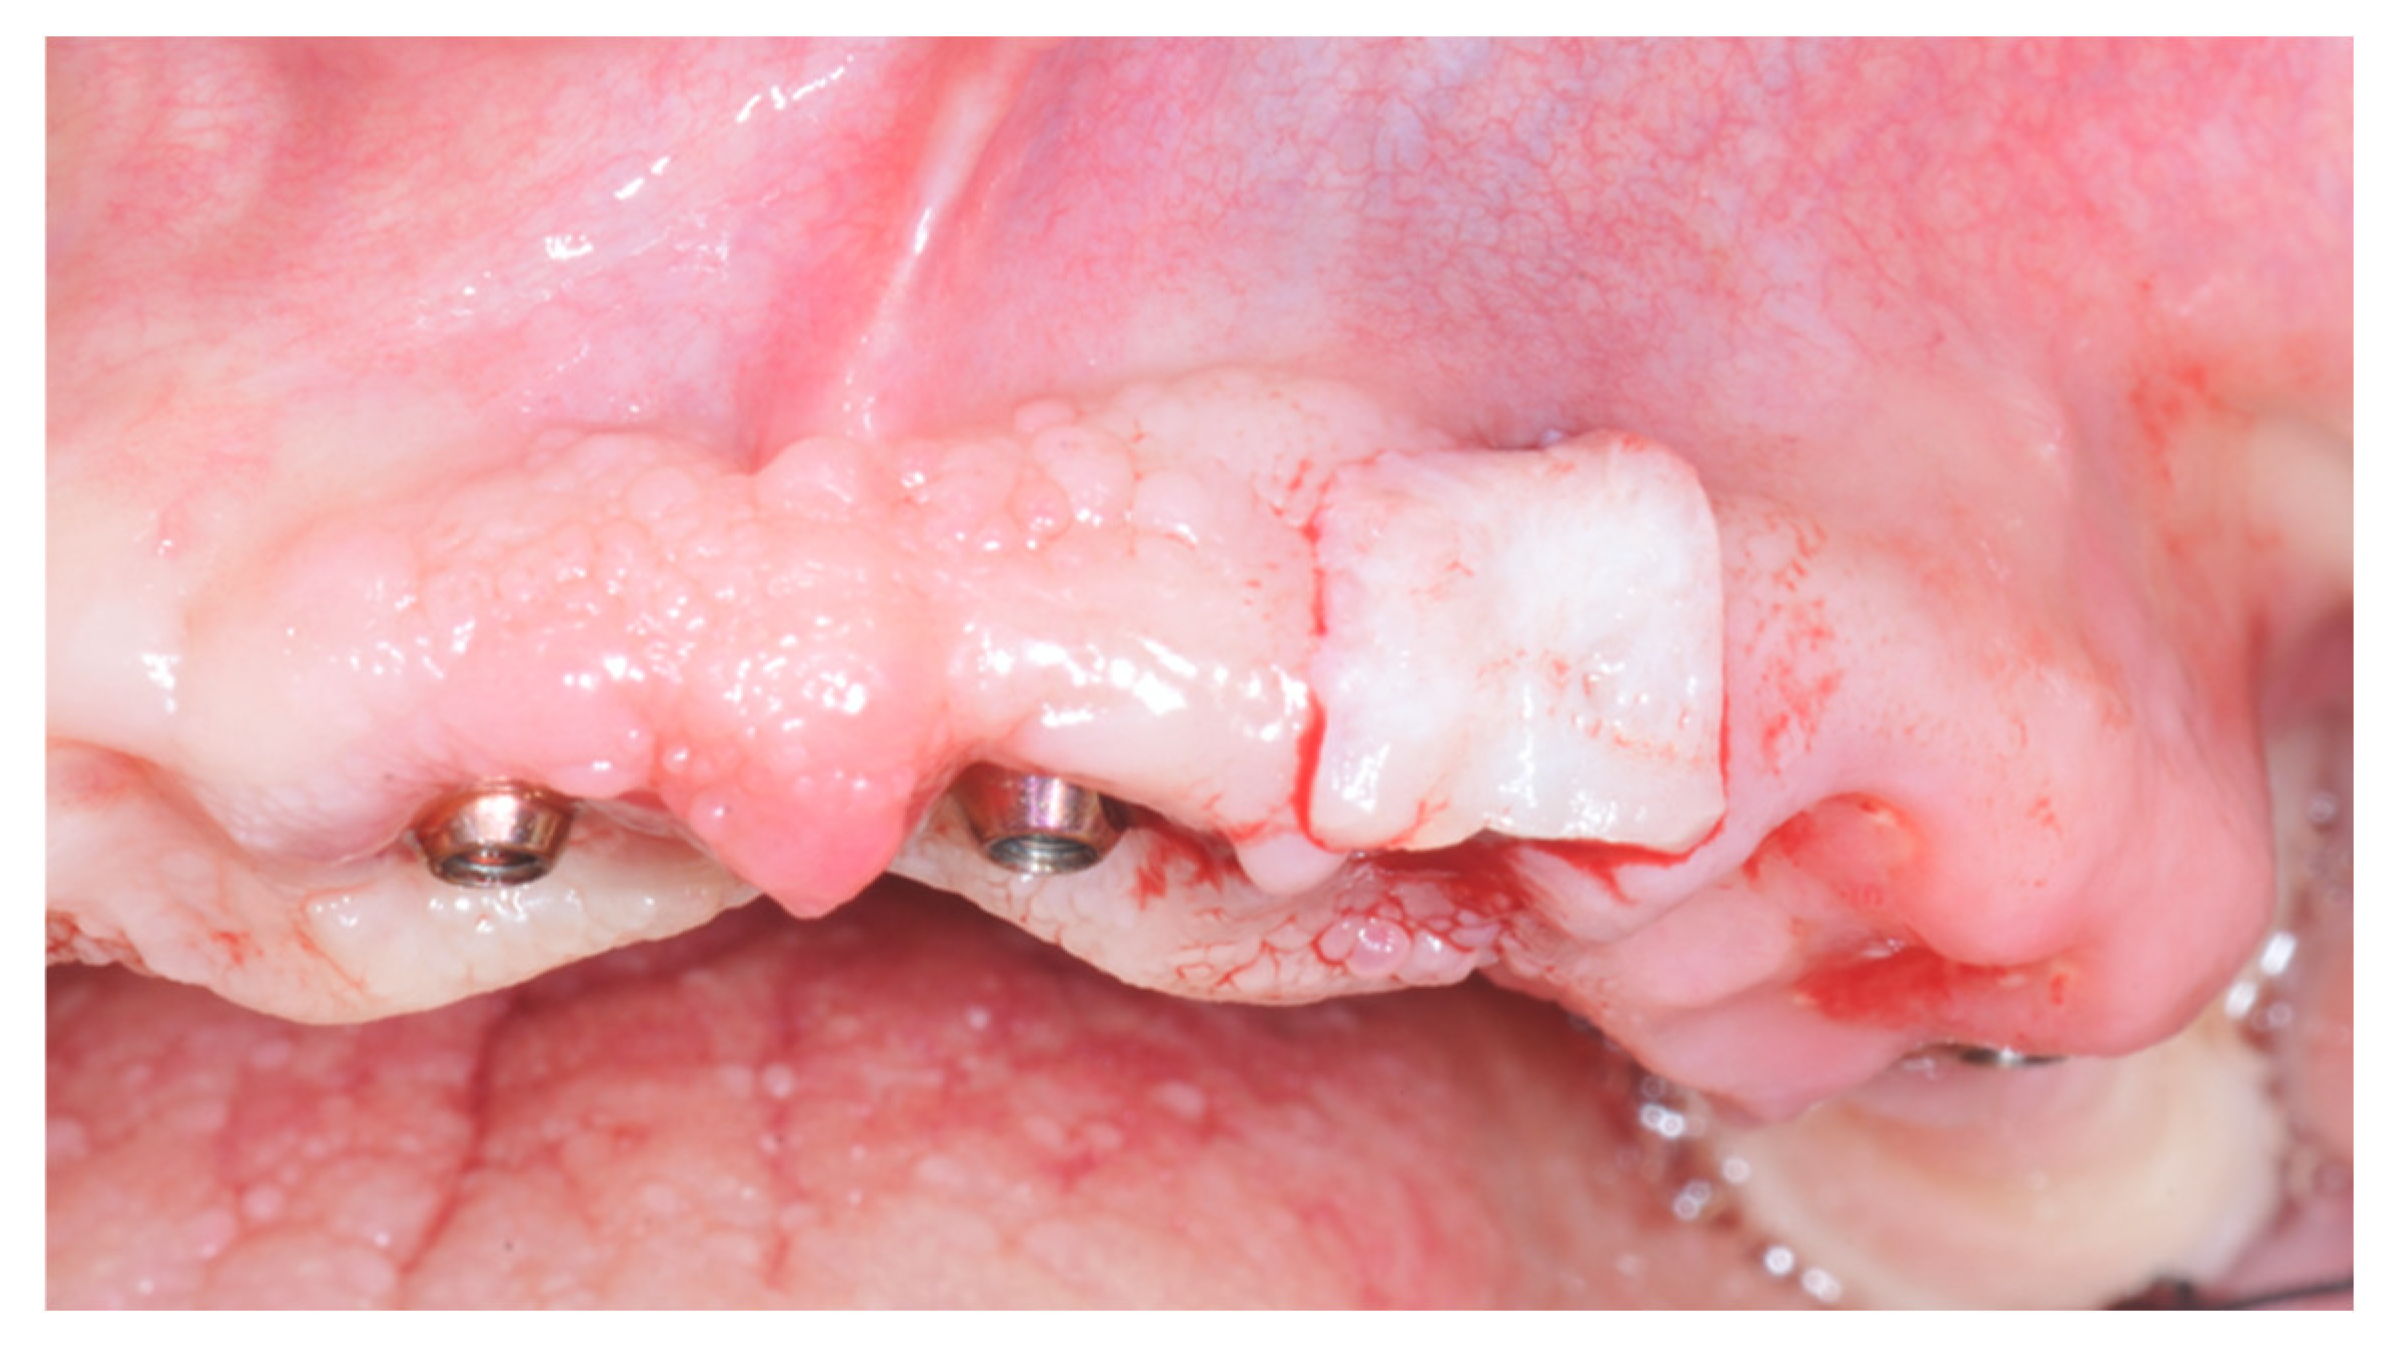

2. Materials and Methods